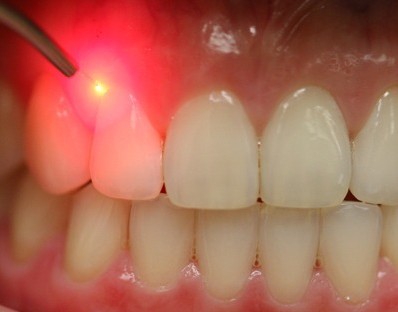

- Lasers are controlled source of light that has been used widely in various fields and in dentistry it offers plenty of advantages

Indications for laser dental treatment

Minor surgeries, gum procedures ,surgeries in medically compromised patients, cosmetic procedures like bleaching, lightening of dark gum and pain relief can be quick and painless with lasers.

Advantages of lasers

- There is no bleeding and no need to give sutures and messy packs can be avoided

- Quick and instant results help in reducing the treatment time.

- Unnecessary antibiotics and pain medications can be avoided.

- Patients can resume normal eating and brushing immediately.

- Can be safely used in pregnant women & patients with pace makers.

What to expect during a laser procedure

Since lasers are high energy sources adequate protective eyewear will have to be worn during the procedure.

What to expect after a laser dental surgery

Most of the time the patient can go back to normal routine the same day.

Antiseptic gels will be given to be applied over the surgery area.

We offer Laser dentistry by world class trained laser dentists . Depending on what sort of treatment you require, there should exist some form of laser dentistry that can address your needs.